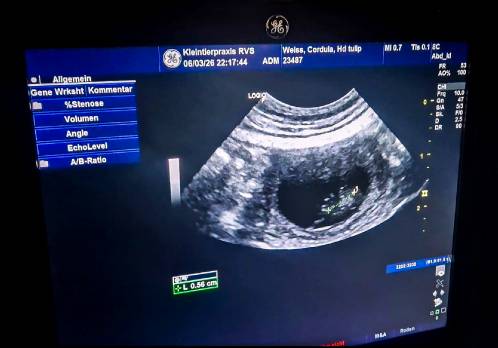

Heute ist Halbzeit. Der 32. Tag von insgesamt 63 einer Hundeträchtigkeit. Und was sieht man??? Nichts! Es ist immer wieder unglaublich, was sich dann in der zweiten Trächtigkeitshälfte doch noch tut! 6. März 2026 Unsere Fahrt nach Nordholland trägt Früchte…. auch wenn sie mit gerade mal 0,5cm noch winzig klein sind!